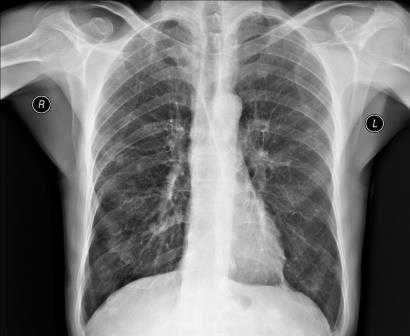

Рентгенография грудной клетки

Для выявления патологических изменений сердца и оценки их влияния на сосудистое русло легких наиболее часто применяют рентгенографическое исследование грудной клетки, позволяющее получить изображение средостения, сердца и легких.

Снимки обычно делаются в заднепередней и левой боковой проекциях. В заднепередней проекции благодаря уменьшению расстояния между сердцем и рентгеновской пленкой изображение сердца получается более четким и менее искаженным, чем в переднезадней. У лежачего пациента можно воспользоваться передвижным рентгеновским аппаратом, но он позволяет делать снимки только в переднезадней проекции.

Нормальная картина

В норме на снимках, выполненных в заднепередней проекции, ширина грудной клетки по меньшей мере в 2 раза превышает поперечный размер сердца. В то же время в переднезадней проекции относительные размеры и положение сердца могут быть другими; возможно усиление тени сердца и дуги аорты. Когда исследование проводится с контрольной целью, рентгенограммы грудной клетки должны подтверждать правильное положение катетеров и водителей ритма.

Отклонение от нормы

Для диагностики заболеваний сердца необходимо оценивать рентгенограммы грудной клетки с учетом данных анамнеза, физикального обследования, ЭКГ и предыдущих рентгенологических исследований.

Изменение формы сердца обычно заключается в увеличении левого или правого желудочка, левого предсердия или даже нескольких полостей. При увеличении левого желудочка в заднепередней проекции левая граница сердца становится круглой и выпуклой с боковым расширением в своей нижней части, а в боковой проекции определяется выбухание левого желудочка кзади. При увеличении правого желудочка в заднепередней проекции наблюдается вторичное изменение левой границы сердца за счет расширения тени легочной артерии, а в боковой - расширение тени выносящего тракта правого желудочка. При увеличении левого предсердия его плотность на рентгенограмме в заднепередней проекции увеличивается вдвое, левая граница сердца сглаживается, левый главный бронх смещается кверху. В редких случаях правая граница сердца над проекцией правого желудочка расширяется кнаружи. В боковой проекции определяется выбухание левого предсердия кзади. Начальными признаками застоя в малом круге кровообращения на снимках, сделанных в заднепередней проекции, являются расширение тени легочных вен в верхнебоковой части корней легких и сосудистые тени, расположенные горизонтально вдоль нижней части правой границы сердца. Хроническая легочная венозная гипертензия приводит к формированию рисунка по типу оленьих рогов (из расширенных верхних и нормальных или суженных нижних легочных вен). При остром отеке легких увеличение плотности в центре легочных полей может по форме напоминать бабочку. Интерстициальный отек легких может напоминать снежные хлопья на фоне легочных полей.